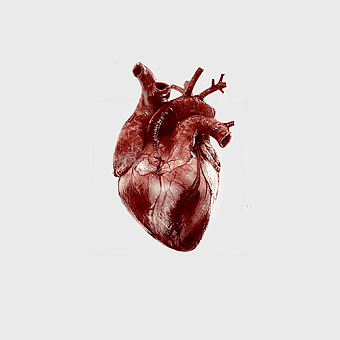

red heart anatomy, human heart drawing, cartoon heart illustration, love and biology, cardiovascular system diagram, medical art depiction, organ structure visualization -

human heart anatomy, cardiac muscle illustration, circulatory system model, heart health visual, cardiovascular organ diagram, medical heart image, visceral structure depiction -

Heart Anatomy Drawing, human heart illustration, human anatomy art, organ depiction, cardiovascular system, medical illustration, anatomical sketch -

human heart anatomy, superior vena cava illustration, systemic circulation diagram, heart rate visual, cardiovascular system study, medical organ depiction, human body organ reference -

human heart anatomy, cardiovascular system illustration, medical heart diagram, heart organ structure, human body organ visuals, anatomical heart drawing, heart health -

human heart diagram, cardiovascular system anatomy, blood vessel chart, free body diagram, circulatory system illustration, medical organ visualization, human anatomy study -